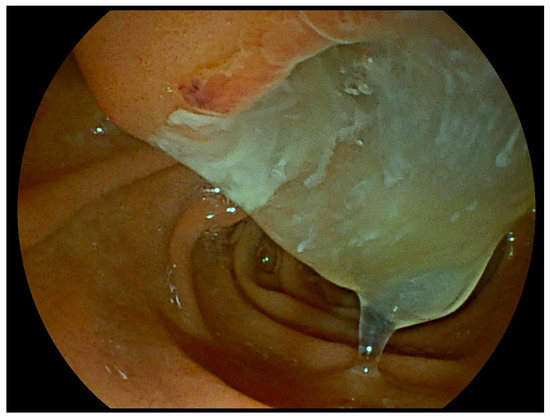

2.4. Fish Mouth Papilla

| Fish mouth papilla | IPMN | Endoscopy | - <30% of cases - More common in main-duct and mixed IPMN - Best assessed by duodenoscope |